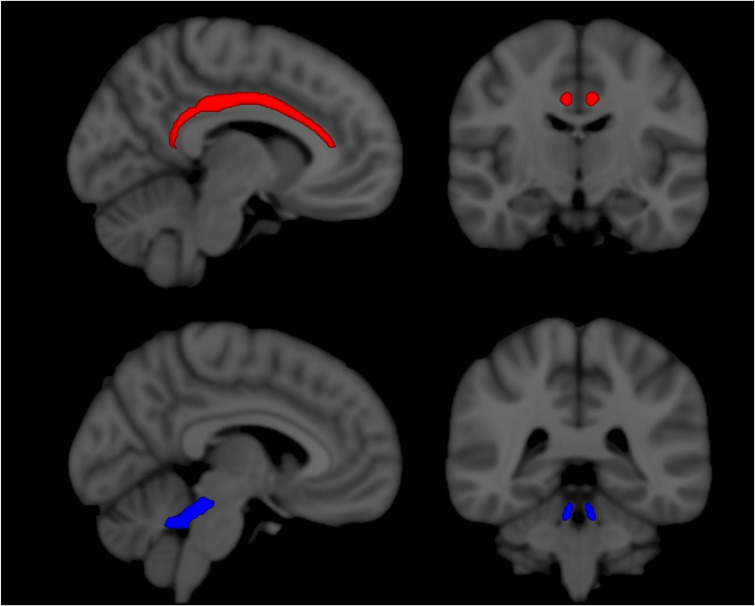

Results: Radial diffusivity in the cingulum and cerebellar peduncles showed a significant difference in rate of change between treatment and placebo groups (2.7-7.4 × 10-3 mm2/s per 24-week time period, p < 0.04). Radial diffusivity was unchanged (declined) in the treatment (placebo) groups, consistent with preservation (deterioration) of tissue integrity.

Conclusion: Our results suggest that the diffusion tensor imaging of the cingulum and cerebellar peduncles may be useful target outcome metrics in neuroprotective trials in progressive multiple sclerosis.